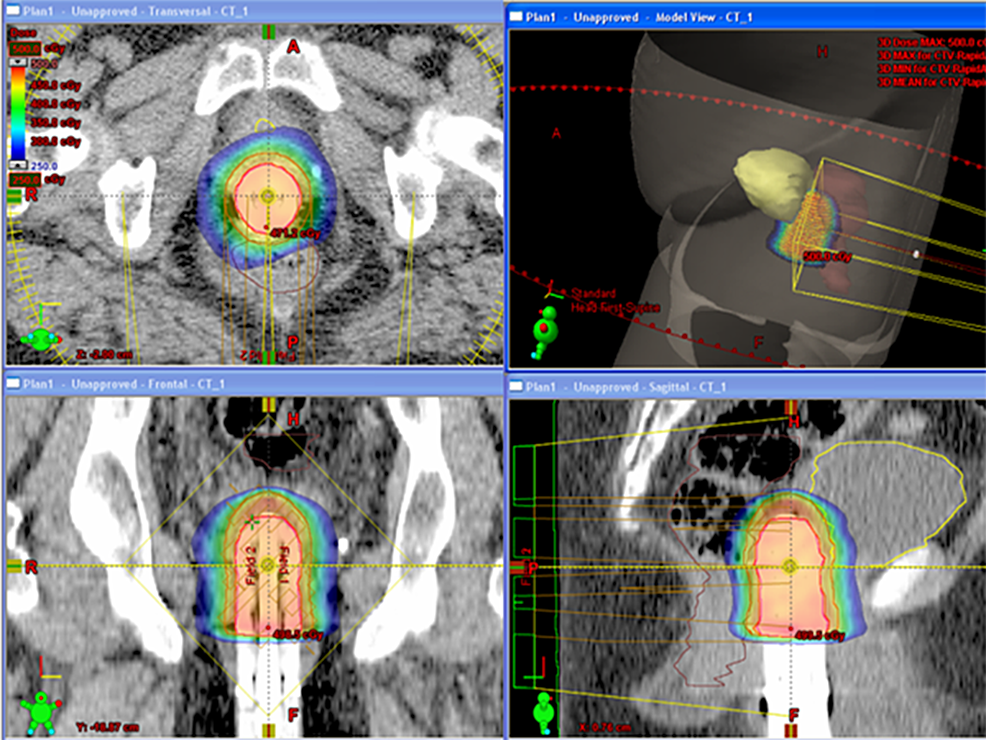

From www.cureus.com

Cureus Stereotactic Body Radiosurgery Using Volumetric Arc Therapy as Radiosurgery Gynecological Cancer Findings from this systematic review suggest that in carefully selected patients with gynecologic cancer and limited macroscopic disease. A growing body of data supports the use of sbrt for oligometastatic/oligorecurrent gynecologic malignancies for. Reported survival outcomes of sbrt for a cohort of 30 patients with recurrent gynecological cancer. Radiosurgery Gynecological Cancer.